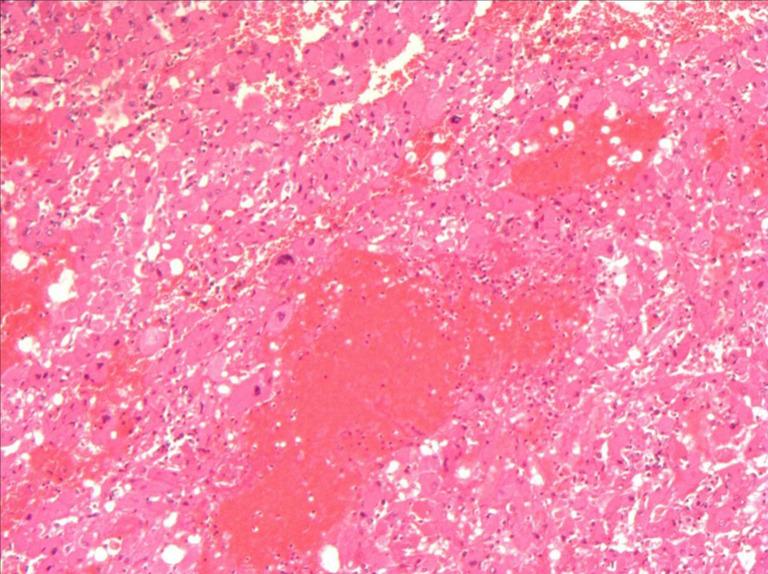

Hepatic epithelioid angiomyolipoma (HEAML) is a rare mesenchymal neoplasm that can occasionally exhibit malignant behavior, such as postoperative recurrence or distant metastasis. Most HEAML patients are female, and it is difficult to distinguish them from other liver tumors. The diagnostic accuracy rate is less than 32%. We present a case of HEAML in an elderly woman with mild fatty liver, without a history of hepatitis, tuberculosis. The patient underwent early laparoscopic liver tumor resection.

肝上皮样血管平滑肌脂肪瘤(HEAML)是一种罕见的间叶性肿瘤,偶尔可表现出恶性行为,如术后复发或远处转移。大多数HEAML患者为女性,且难以将其与其他肝脏肿瘤区分开来。诊断准确率低于32%。我们报告一例老年女性HEAML病例,该患者有轻度脂肪肝,无肝炎、结核病史。患者接受了早期腹腔镜肝肿瘤切除术。

结论

HEAML这种罕见肿瘤具有一定程度的恶性潜能,主要影响老年女性。CT和MRI上的某些特征有助于其与其他肝内病变相鉴别。在我们的病例中,采用了多模式方法,对肿瘤进行详细的影像学分析可为其准确诊断提供参考。